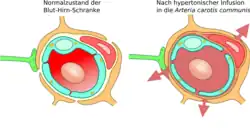

Osmotische Öffnung der Blut-Hirn-Schranke

Kurz nach der Entdeckung der Tight Junctions wurde 1970 die These aufgestellt, dass die Einwirkung von hyperosmotischen Lösungen auf die Endothelzellen die Blut-Hirn-Schranke öffnen könne.[124] 1980 wurde diese Methode erstmals angewendet[125] und 1984 wurde durch elektronenmikroskopische Aufnahmen der experimentelle Beweis für diese These erbracht. Elektronendichte Marker waren durch die Tight Junctions in das Gehirn diffundiert.[126]

Über die Arteria carotis interna werden hyperosmolare Lösungen, beispielsweise von Mannitol oder Arabinose infundiert. Der unterschiedliche osmotische Druck zwischen den Endothelzellen und der infundierten Lösung bewirkt einen Flüssigkeitsverlust in den Endothelzellen, der zu deren Schrumpfung führt. Durch die Schrumpfung entstehen Zugkräfte zwischen den Zellen, was zu einer Öffnung der Tight Junctions und somit zur Öffnung der Blut-Hirn-Schranke führt.[127][128]

Aufgrund des Konzentrationsgradienten zwischen intravasalem und interstitiellem Raum fließt in größerer Menge Wasser aus dem Plasma ins Gehirn zurück (bulk flow). Dadurch werden im Wasser gelöste Moleküle in das Gehirn eingeschwemmt, wobei ein Ödem entsteht.[125][129][130][131][132]

Die durch die Schrumpfung der Endothelzellen bewirkte Öffnung der Tight Junctions beträgt etwa 20 nm.[132] Dadurch können Moleküle mit einem hydrodynamischem Durchmesser von ebenfalls etwa 20 nm in das Gehirn eindiffundieren.[133] Die Öffnung der Blut-Hirn-Schranke ist bei dieser Methode reversibel. Zehn Minuten bis spätestens zwei Stunden nach der Infundierung ist sie wieder vollständig hergestellt.[123][134] Die Einwirkungszeit der hyperosmolaren Lösung beträgt etwa 30 Sekunden. Durch eine Vorbehandlung mit einem Na+/Ca2+-Kanalblocker kann die Öffnungsdauer der Blut-Hirn-Schranke verlängert werden.